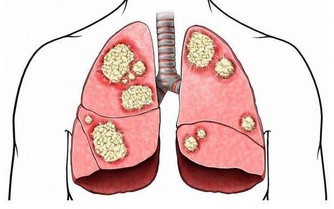

4、多吃黃色蔬菜、紅薯、南瓜、西紅柿和胡蘿蔔等新鮮綠色蔬菜,內含豐富的胡蘿蔔素,

對兒童及成人均有重要的提高免疫力、減少感染、減低腫瘤發病機會的作用。

5、多喝綠茶及多吃深綠色蔬菜、飲料以茶最好,茶以綠茶最佳。

綠茶有明確的抗腫瘤、抗感染作用,品茶能放鬆身心,釋放壓力。